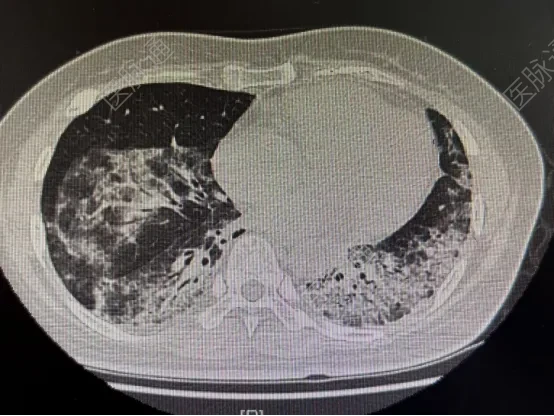

HRCT:双肺及胸膜下区域见广泛网格影、蜂窝样改变及牵拉性

肺部CT:示双肺胸膜下网格影、蜂窝样改变